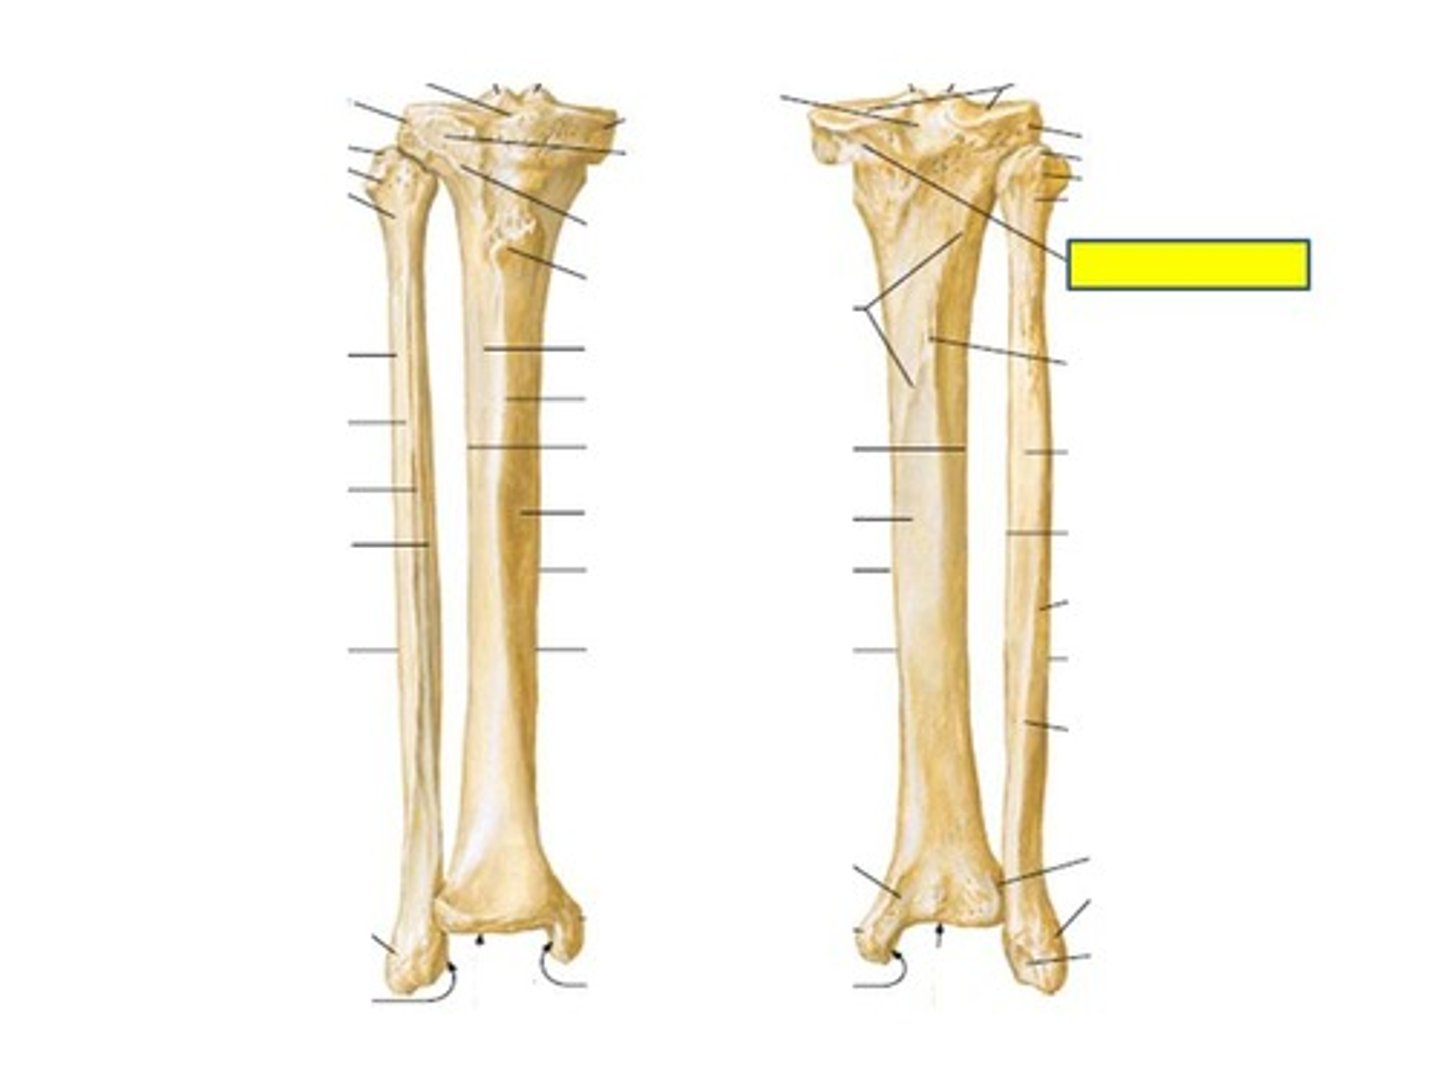

Head of tibia

#1

Medial condyle

Lateral condyle

Fibular articular facet

Medial tibial plateau

Lateral tibial plateau

Intercondylar eminence

Anterior intercondylar area

Posterior intercondylar area

Tibial tuberosity

Semimembranosus sulcus

Gerdy's tubercle (anterolateral tubercle)

Soleal line

Medial malleolus

Articular facet of medial malleolus

Tibial plafond

Inferior articular surface

Fibular notch

Head of fibula

Neck fo fibula

Lateral malleolus

Malleolar fossa

Articular facet of lateral malleolus